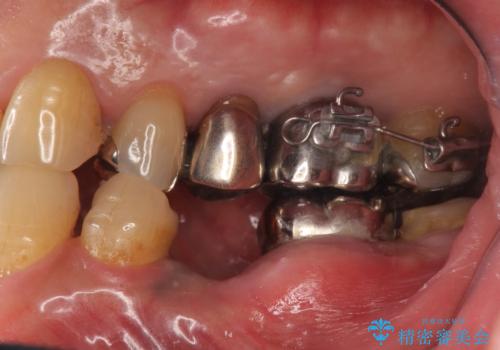

- 他院で奥歯が割れている為抜歯が必要と言われたとのことで来院。

右上56および左下5は割れていたためやむなく抜歯しインプラントにしていきました。

左下7(一番奥の歯)は抜歯をせずに済みましたが、高さがないため上の歯を矯正治療で沈め、また、歯ぐきの手術を合わせて行いクラウン(被せ物)をしっかり入れる処置をおこなっています。